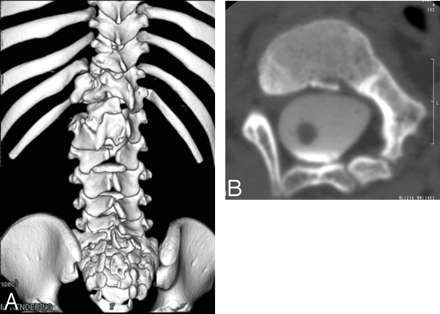

On admission, physical examination revealed a left lower limb weakness (4/5), spasticity, and atrophy. There was a small dermal sinus rostral to the anus, without communication to the intradural region. CT of the spine revealed a spina bifida at the L2 to S2 levels, and there were congenital vertebral anomalies associated with hypoplasia of T12 and L1 (Fig 1A, -B). MR imaging revealed the presence of a split cord beginning at the L2 vertebral body level in a single dural sac, and the distal thecal sac was widened (Fig 2A). A tethered cord was seen at the L5 level (Fig 2B). The right hemicord had an intradual connection to the upper cord and a relatively normal configuration. On the other hand, the proximal part of the left hemicord, with an aberrant course anterolaterally in the spinal canal, was tapered to a point of complete absence of the dural sac (Fig 2C–E) and had no apparent intradual connection to the upper cord. The distal part of the left hemicord resumed a normal appearance and presented the lateral set of nerve roots arising from the left hemicord (Fig 2F). CT myelography showed the left hemicord with the small remnant of subarachnoid space running through the intravertebral cleft at the level of spinal anomalies (T12–L1) (Fig 3). Above this region, neither the subarachnoid space nor spinal cord could be defined by CT myelography or thin-section MR images. Thus, detailed and repeated preoperative radiologic examination failed to reveal the continuity of the left hemicord to the right side and the upper cord, though there was an extradural neural tract through a canal in the deformed vertebrae (Fig 4).

A, 3D spinal CT reconstruction of the spinal column shows spina bifida from L2 to S2 and a congenital spinal anomaly associated with hypoplasia of L1, T11, and T12.

B, CT myelography axial scan shows a congenital spinal anomaly associated with hypoplasia of L1.